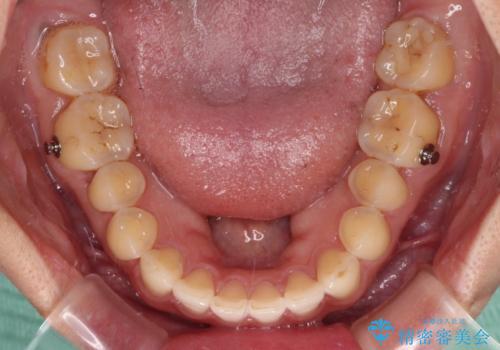

すきっ歯はあっという間に後戻りを起こすので、可及的に後戻りを防止するために、上下前歯部を舌側からワイヤーで固定しています。

通常は下顎前歯のみに行っていますが、空隙歯列弓では上顎でも行っています。